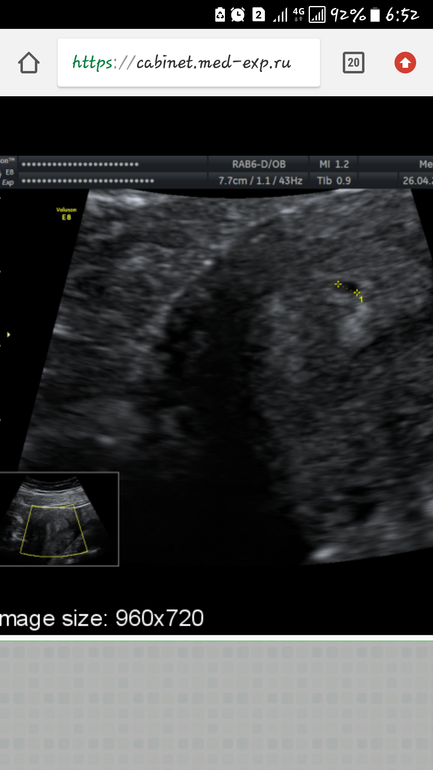

Я вижу измерения пя в матке.почему вб?есть подозрения?

Да.мне сказали в яичнике 2 жт. И в трубе что то непонятное не поймут что пока

Я так понимаю что подозрение на второе пя.такое вполне возможно.толтко ждать.но одно пя у вас точно в матке